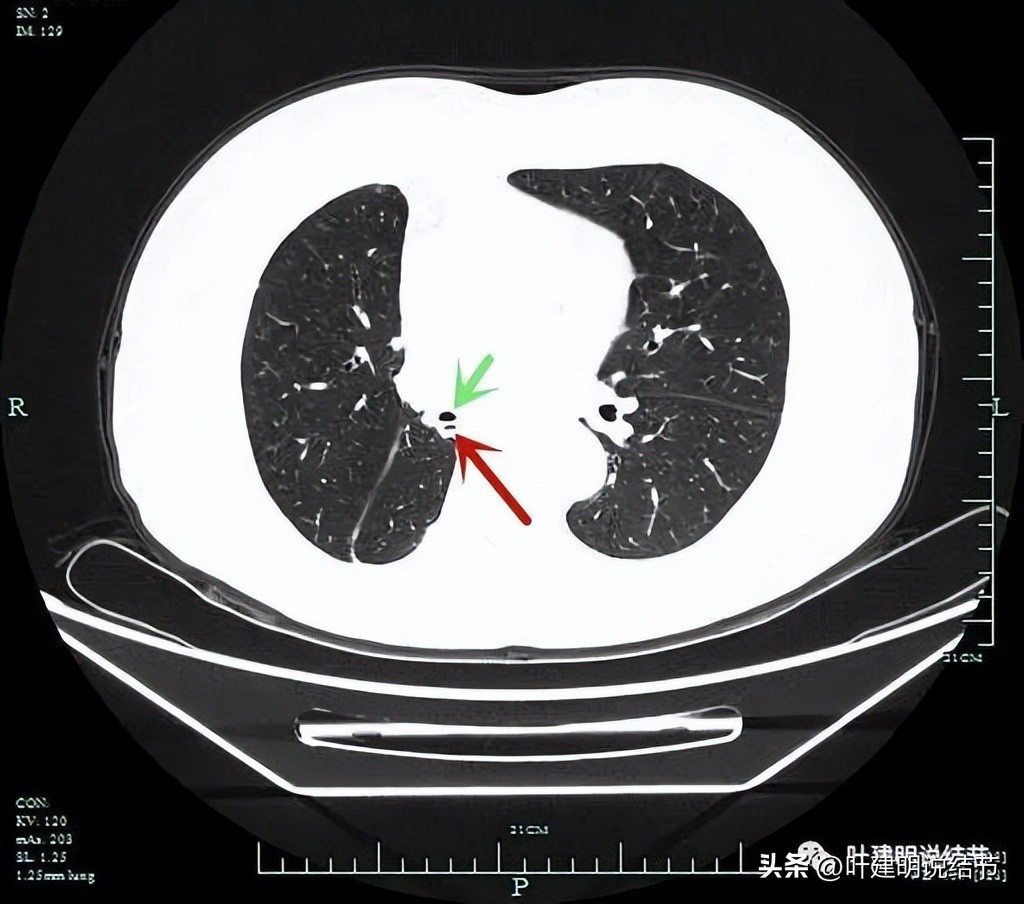

上图示右侧下叶切除后支气管残端(红色箭头);绿色箭头是中叶支气管开口。